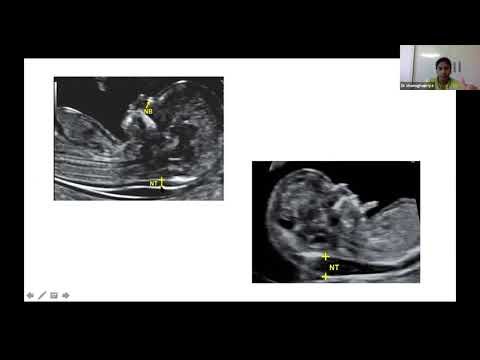

• CDE Series (3) Pregnancy & Screening : NT Scan & Anomaly Screening